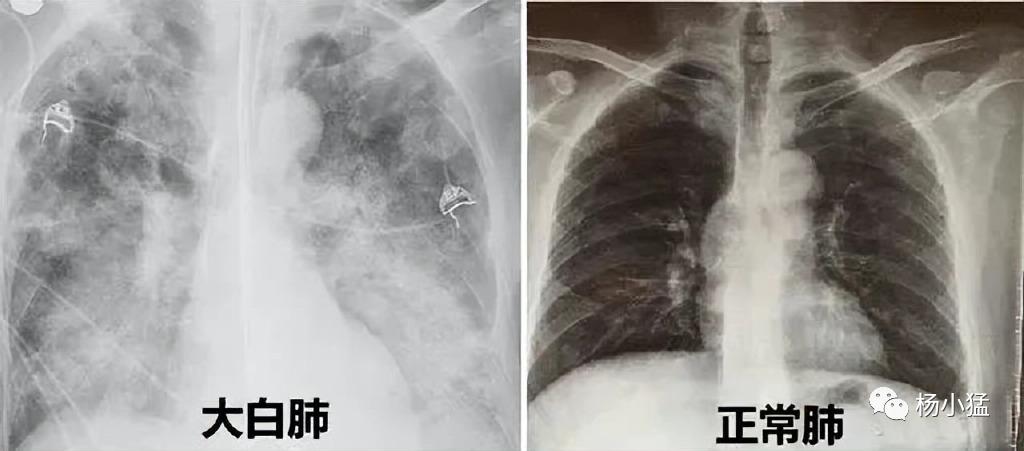

白肺是肺部影像学表现的一个口语化描述,当肺部出现炎症和感染时,肺泡被渗出液等填充,在影像学(如CT)上的表现就是出现白色区域。

并不是所有的肺部出现炎症就都叫做白肺,一般来讲肺部炎症较重、渗出液较多,白色的影像区域面积达到一定比例(70%~80%)时,在临床上把它称为白肺。

从现代医学角度来看,造成白肺的原因有两个:一是肺部自身的感染,二是身体其他部位的感染诱发人体炎症反应。

新冠病毒的确会对肺部造成一定影响,毕竟新冠病毒的全称可是新型冠状病毒肺炎,但新近的毒株直接导致白肺的概率并不是很高。